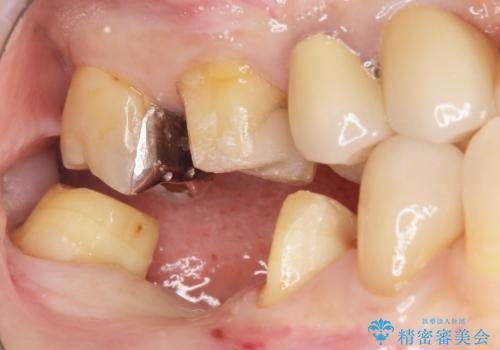

右下の銀歯(右下6)を除去したところ、虫歯が深く保存不可能な状態でした。

抜歯後十分に歯肉の治癒を待ったのち、ブリッジによる補綴治療を行いました。

痛みが出るのが怖い・外科手術は避けたいとのご希望でブリッジをご希望されました。